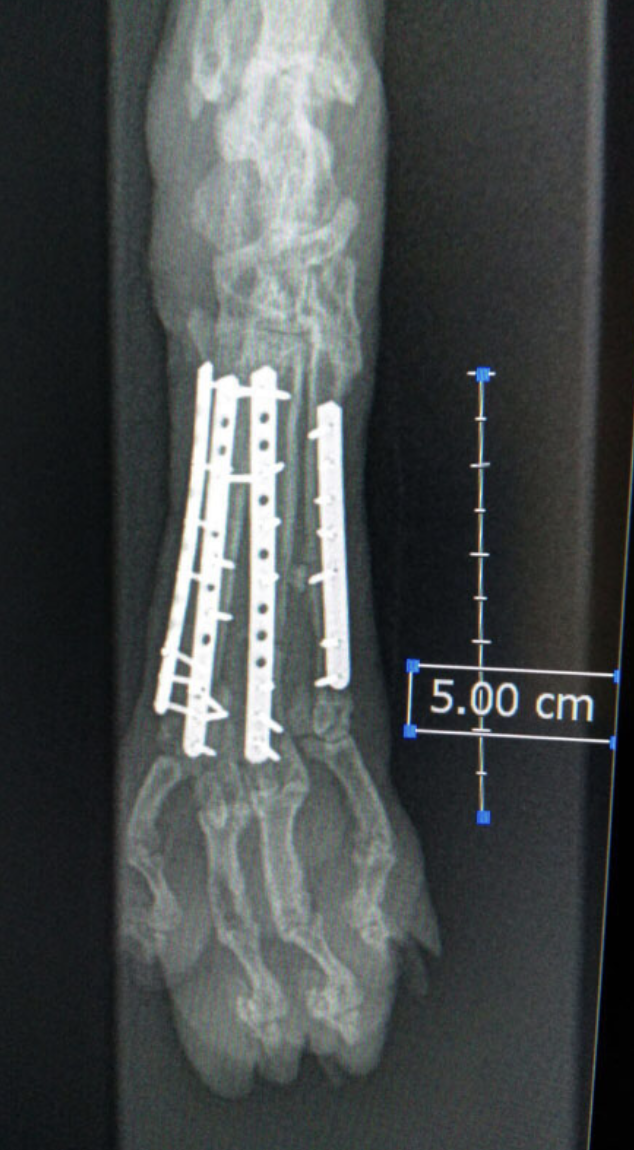

Metatarsal Plating

Example of metatarsal plating.